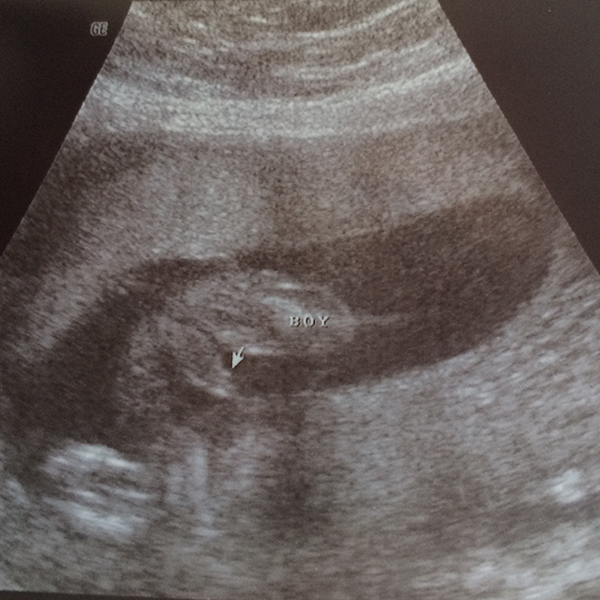

We have a little confession to make. We have been keeping a secret from the internet. If you have seen me in the past few months, you probably already know. If you have talked to anyone that has seen me, they probably already told you, but we are taking it public today! We have been cooking up Baby P #2!! ETA June 17th. I am hoping to make it to the end of the school year, but who knows! We have been enjoying the last 20 weeks with lots of dinners out, family adventures and lots of cuddling. We recently found out if we are having a boy or a girl…check out the pictures to find out what’s in the oven.